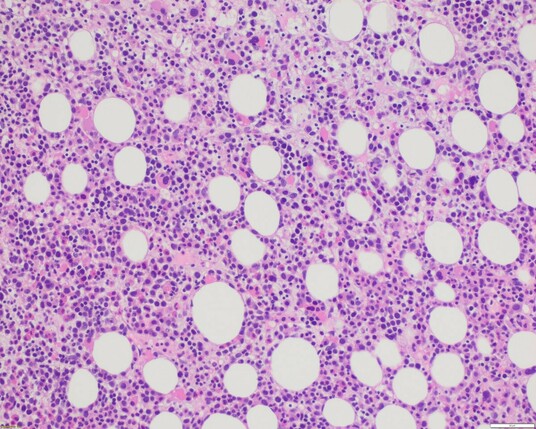

This is the bone marrow of an elderly woman (>65 yr) with marked pancytopenia and progressive transfusion dependency. 🧡 1/

Older lady w/ thrombocytopenia (47K) neutropenia (1.3K), normal Hgb

BM:Meg +erythroid dysplasia,15% ring sideroblasts (iron stain πŸ‘‡πŸ»).

NGS shows an SF3B1 K700E with 4% VAF.